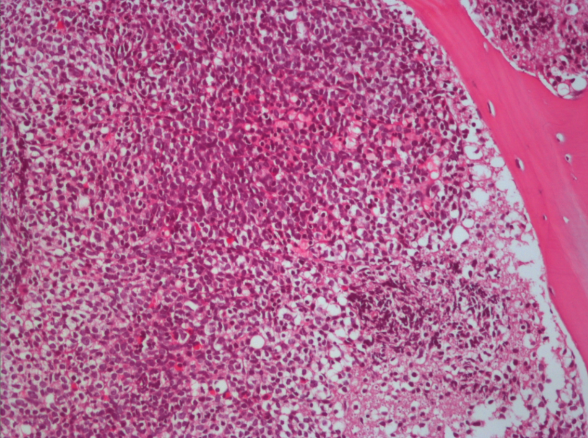

In the analysis of cerebrospinal fluid (CSF) the opening pressure was 370 mmH2O, CSF protein and electrolyte levels were witin normal limits, and there was not pleocytosis, serology and culture were negative. The patient had started to take acetozolamide 750 mg/d and dexametazone 12 mg/d. In the 7th day of treatment the opening pressure of CSF was measured as 290 mmH2O. Cytologic exam of CSF showed atypical lymphoid cells (Figure 3). In bone marrow biopsy, atypical lymphoid cells were diffuzely stained with Pax 5 by immunohistochemical method (Figure 4). The patient was diagnosed as precursor lymphoblastic leukemia/lymphoma. The patient who transferred to the Hematology clinic died on the 26th day of admission because of the sepsis on 20th day of admission.

Figure 4 In bone marrow biopsy specimens, attention was drawn to infiltration of dense atypical lymphoid cells among bone specimens. (Hematoxilen Eosin X 200).